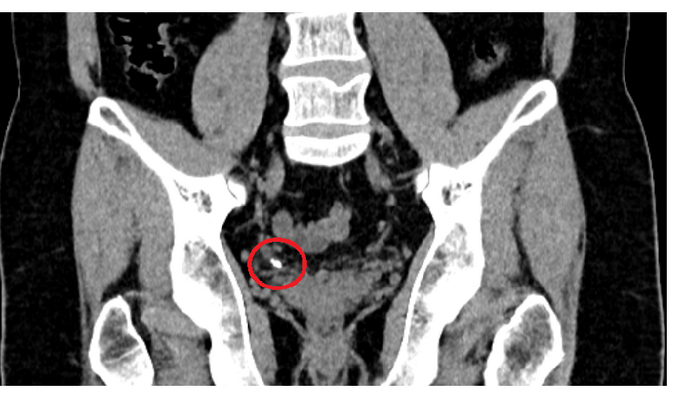

Мазок на инфекции, УЗИ, Сумамед "на всякий случай". Мазок - это тоже больно. Это такой ёршик, который тебе прямо туда засовывают. Но не так больно, как писать. Анализы хорошие, а вот УЗИ... Песочек у меня. Не камни - много мелкой фракции. Видимо что-то покрупнее проскочило наружу, оцарапало мочеточник, воспалилось и теперь болит.

Что делать? Пейте толокнянку по паре столовых ложек в качестве мочегонного. И ждите пока всё выйдет. Потом снова на УЗИ. И я пью. Неделю пью. Две пью. Болит уже не только член. Больно теперь еще и внутри. Иду снова к доктору. Снова УЗИ.